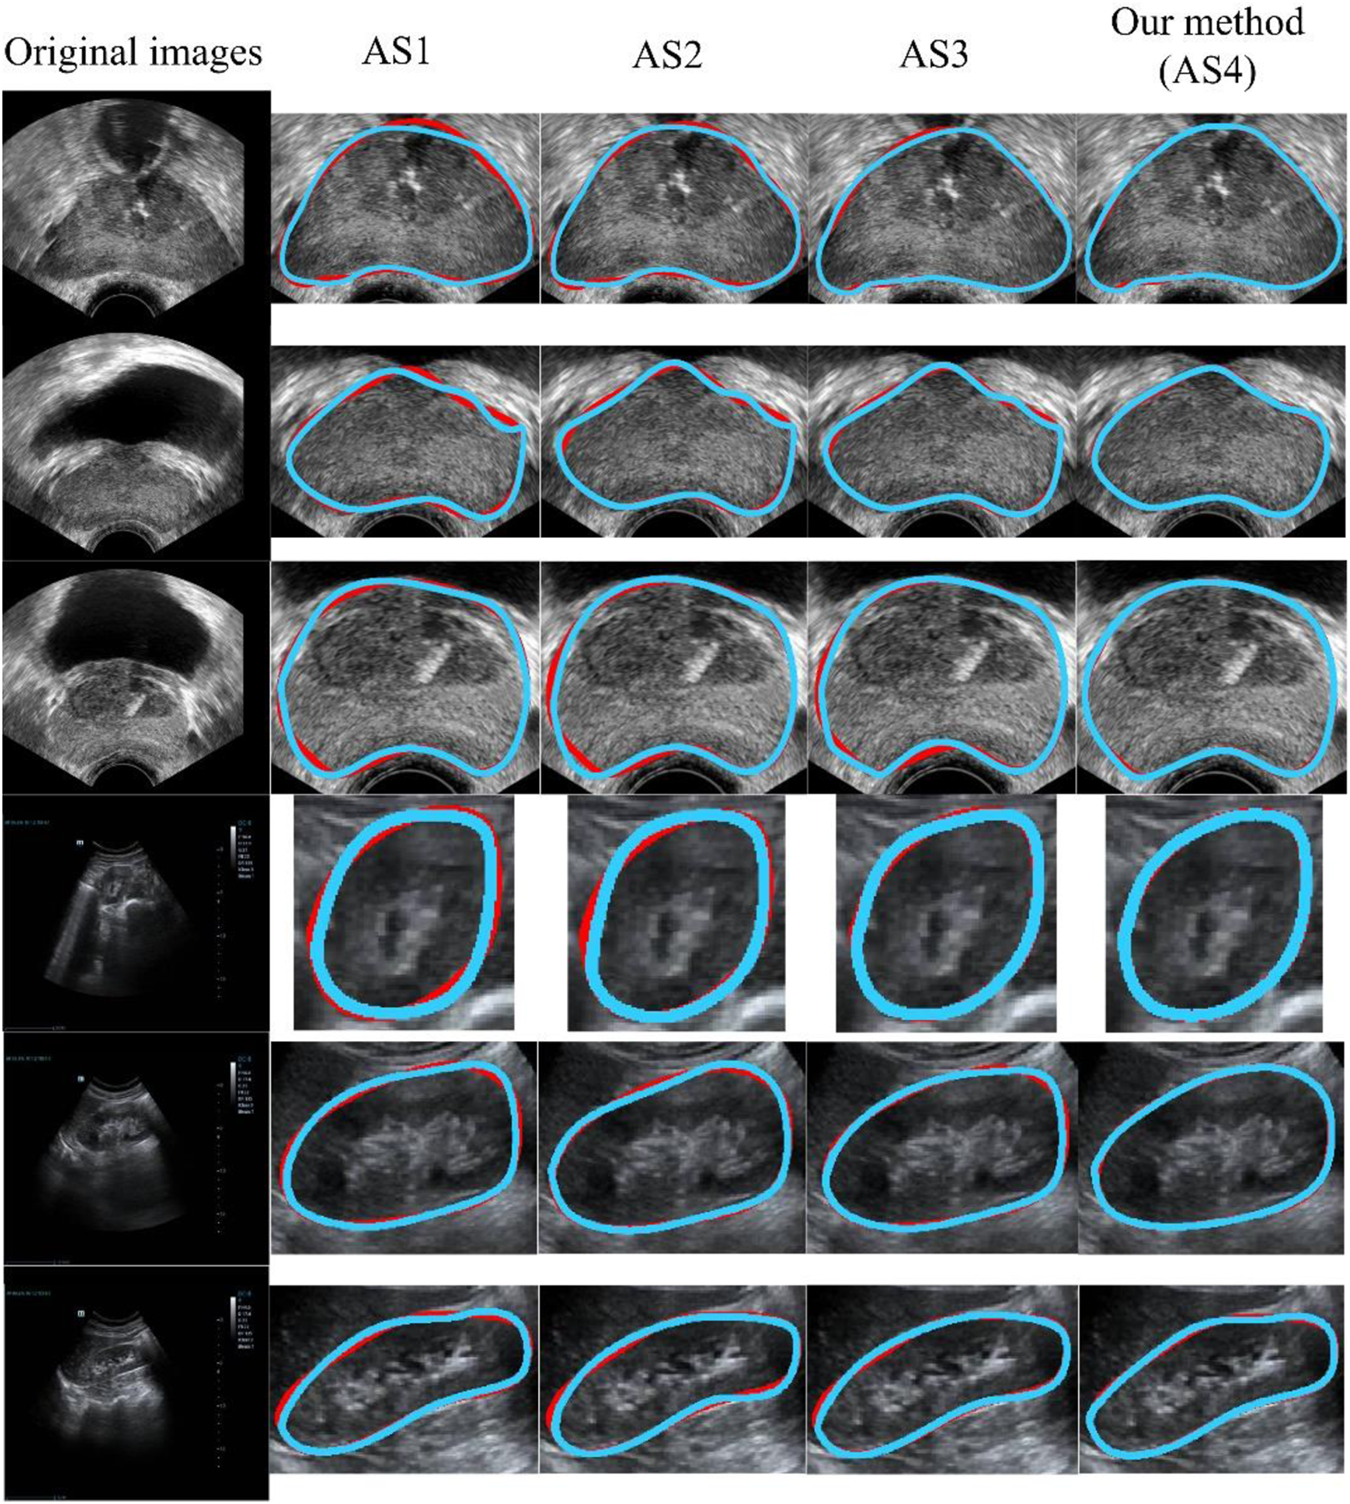

Our model (AS4) had the optimal results, with DSC, OMG, and ACC values of 95.7% ± 2.4%, 94.6% ± 2.6%, and 95.3% ± 2.6%, respectively. Figure 8 presents a visual comparison of three randomly selected segmentation outcomes. The first three rows show the results of randomly chosen prostate cases, and the last three rows show the results of kidney cases. Table 7 represents the corresponding quantitative outcome of each qualitative outcome in Figure 8, where various evaluation metrics, including DSC, OMG, and ACC are adopted for assessment.

FIGURE 8

Qualitative results using different ASs. The blue and red curves show the experimental results and ground truth, respectively. From AS1 to AS4, the performance increased progressively. AS4 represents our method. All of the methods (AS1-AS4) included the preprocessing stage. AS: ablation study.